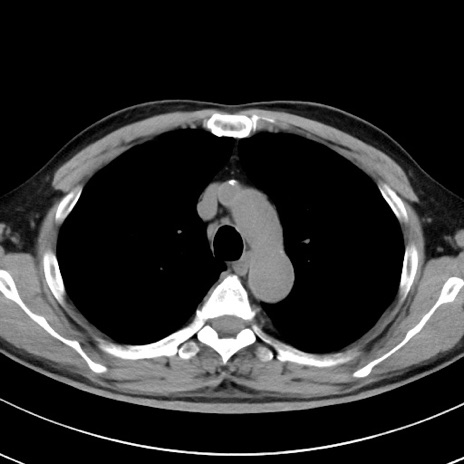

【腹部TIPS】症例29 参考症例 CT(横断像)

症例

70歳代男性